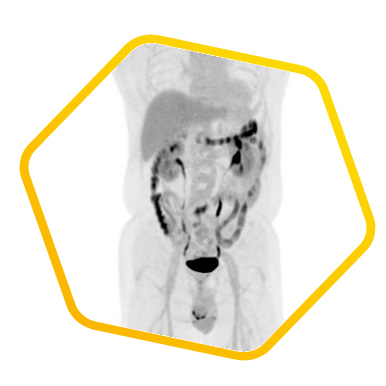

Dual tracer PET/CT (F-18 FDG and Ga-68 DOTATATE) are used for the metastatic evaluation of neuroendocrine tumor.

![]() [F-18] FDG |

![]() [Ga-68] DOTATATE |